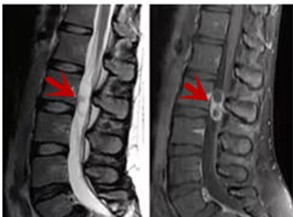

利器三:MRI(核磁共振)

MRI利于磁场和射频脉冲使体内的氢原子核发生磁共振现象而产生的图像,对软组织的分辨率很高,对于脊髓、椎间盘、神经、血管、韧带、骨髓、腰部肌肉及周围软组织有很好的显示效果,可以清晰的显示腰椎间盘突出对硬膜囊、神经根压迫程度,以及骨折是陈旧还是新鲜,同时在脊髓病变(如脊髓损伤、髓内出血或肿瘤)、椎管内脓肿/血肿、椎旁肌肉软组织病变等方面也具有优势,但是检查时间较长,部分患者可能因体内金属植入物(如心脏起搏器、人工耳蜗等)而无法进行检查。

箭头提示腰椎管内肿瘤

红色箭头提示新鲜骨折,黄色箭头提示陈旧性骨折